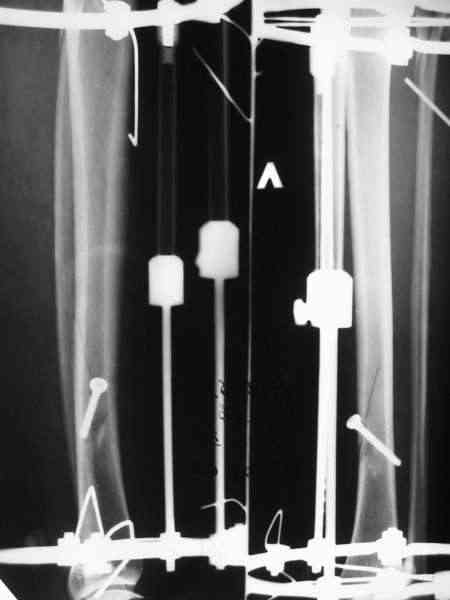

Там не просто "всего 1 пара колец" - там еще и компрессирующий винт, который выполняет функцию спиц с встречными упорами. Эти два кольца могут быть на начальном этапе лечения напряжены на дистракцию, так что могут противостоять большим осевым нагрузкам.

Мы лет 5-6 назад, когда еще не делали закрытое штифтование, сделали с десяток подобных операций, в том числе несколько на бедре. Репозиция закрытая, кортикальный винт 4,5 мм через прокол. Ближний кортекс рассверливали до 5 мм после нарезания резьбы, то есть получался нормальный компрессирующий винт. Аппараты только уже делали монолатеральные стержневые, чтобы не прошивать насквозь мышцы спицами (пример в приложении).

Хотя, конечно, вполне можно и обычные кольца со

спицами.